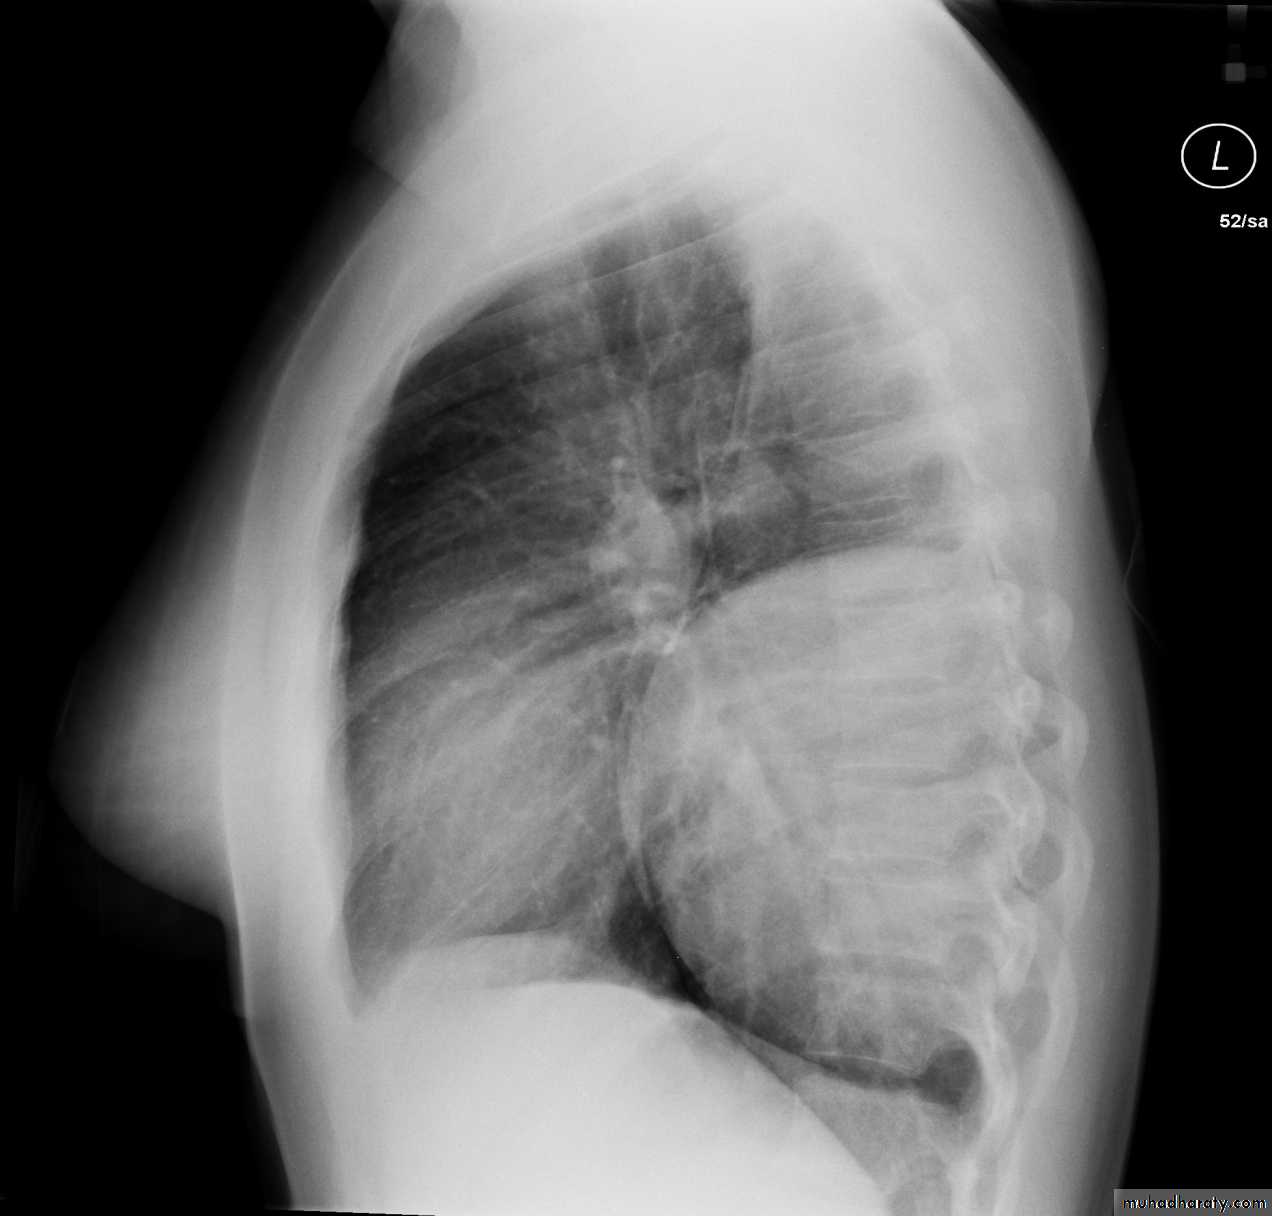

Hodgkin lymphoma of te middle mediastinum